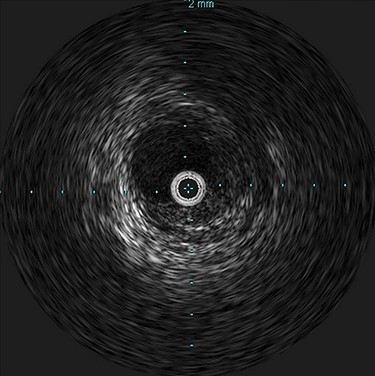

She was admitted and maintained on bowel rest and heparin infusion. Given persistent pain after 2 days of non-operative management, an abdominal arteriogram was performed through a left axillary artery cutdown. The dissection was identified 1.5 cm distal to the origin of the SMA (Fig. 2). Intravascular ultrasound was used to determine diameters and landing zones for stent placement (Fig. 3). The dissection was initially treated with a 6 mm × 40 mm self-expanding stent followed by post-dilation with 4 mm × 40 mm and 6 mm × 40 mm balloons. A 5 mm × 19 mm stent graft was deployed proximally with small overlap and ~3-mm extension into the aorta. Completion angiogram showed <10% residual stenosis (Fig. 4). As the right external iliac artery dissection was small and asymptomatic, no intervention was performed.

Post-stenting angiogram of the SMA demonstrating preservation of the middle colic artery as well as the distal branches of the SMA.